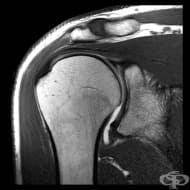

ЯМР на рамо

MRI е отличен избор за изследване на раменната става. Чрез изследването се получават ясни изображени...